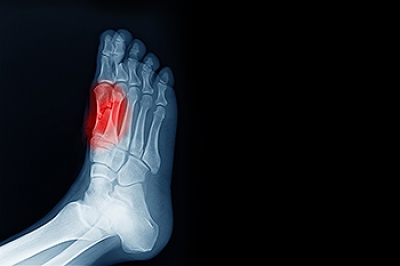

Your feet are a critical part of your overall health, and our podiatry services focus on diagnosing and treating disorders of the lower extremity to ensure your feet remain healthy and functional. We provide diabetic foot care and treat a range of issues, including foot and heel pain, bunions, hammertoes, fungal nails, plantar fasciitis, ingrown toenails, ankle pains, varicose veins, and leg swelling. We use advanced surgical techniques to correct foot problems and minimize scarring, specializing in bunion and hammertoe surgery, as well as Achilles' tendon repair.